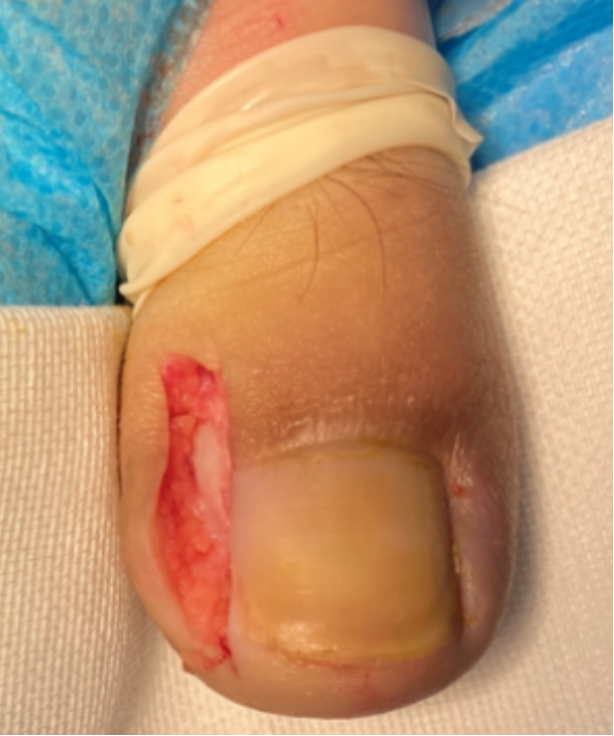

2.鱼嘴切除:把趾甲前侧缘,最容易嵌甲的地方,切掉5mm宽的皮肤,再缝合起来,这样就能把甲侧缘的组织拉下来,使里面被包裹的嵌甲暴露出来。